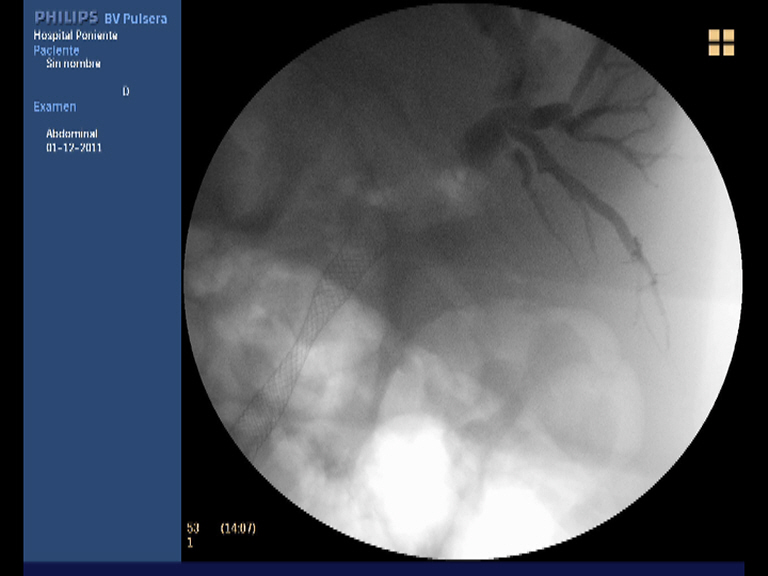

Paciente varón de 60 años de edad, sin antecedentes de interés que presenta dese hace un par de meses pérdida de peso importante (10 kgr), molestias epigástricas vagas junto a coluria e ictericia progresiva. Analíticamente destaca una BRT de 16 mgr/dl, a expensas de la fracción directa (8.21 mgr/dl), con ligera hipertransaminemia (GOT 68 UI/L, GPT 74 UI/L), GGT 1115 UI/L, FAT 558 UI/L e hiperlipemia mixta. El Ca 19.9 se encontraba a unos niveles de 242 UI/dl. Se practica una ecografía abdominal con el hallazgo de una masa en la cabeza pancreática de 3 x 2.7 cm, hipoecoica e irregular que obstruye el colédoco (dilatación retrógrada de unos 11 mm) junto a dilatación de la vía biliar intrahepática, vesícula dilatada (Courvoisier) sin adenopatias evidentes. El TAC trifásico realizado unos días después confirmando la existencia de la masa descrita a nivel de la cabeza pancreática (3 cm), que contacta con la pared duodenal, pero no infiltra la vena porta ni la VMS. Múltiples adenopatías de entre 5 y 1 cm adyacentes al tronco celíaco y peripancreáticas. Él colédoco y la vía biliar intrahepática se encuentran muy dilatadas, así como la vesícula biliar y el conducto pancreático. Con el diagnóstico de posible adenocarcinoma pancreático T3-N1-M0, se realiza una USE radial en nuestro centro, donde además de lo ya observado (la masa no obstante es de mayor tamaño 3.5 x 4 cm) en las anteriores pruebas diagnósticas, se confirma la infiltración de la VP y la confluencia con la VMS. El tronco celíaco y la AMS están libres de afectación tumoral. También se observaro varias adenopatías en el TC y peripancreáticas. Dado los niveles de BRT se decide colocar una prótesis biliar completamente recubierta por CPRE como drenaje biliar. Finalmente, para la confirmación histológica de la neoplasia, se realiza una USE-PAAF. El análisis citopatológico confirma la presencia de células malignas, aunque no se especifica la extirpe (quizás por la poca experiencia que aún se tiene en el estudio citológico).